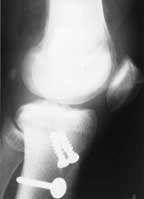

The left hand x-ray is of a patient’s knee before an anterior cruciate ligament reconstruction and meniscus repair that were performed at another orthopaedic Center. The patella is in the normal position. The right x-ray is of the same knee just 4 weeks following surgery after the patient was referred to our Center with significant quadriceps atrophy and limited knee motion and patellar mobility. You can see that the patella has dropped significantly.